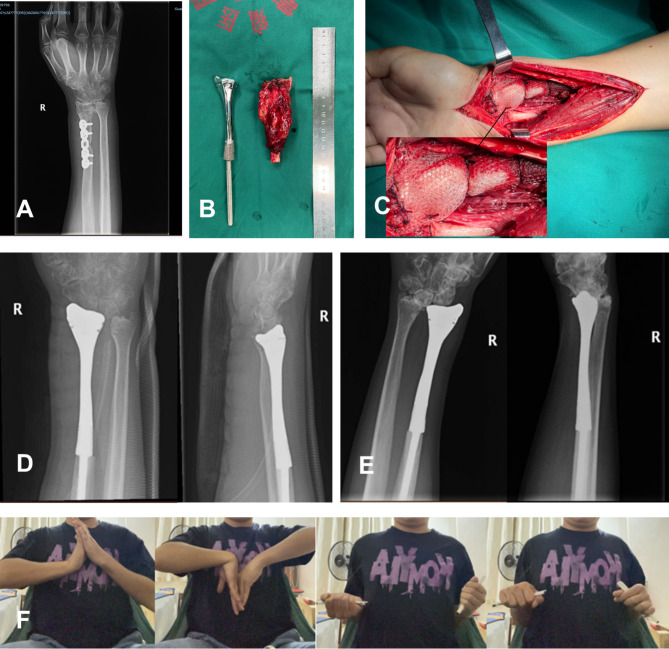

Objective: This study introduces a surgical technique involving the use of 3D-printed all-metal prostheses combined with mesh patches for the treatment of distal radial giant cell tumors, analyzing and evaluating the midterm outcomes for patients undergoing this treatment. The experience provides insights into the application of prosthesis replacement for reconstructing distal radial defects.

Methods: From January 2018 to January 2021, our center treated five cases of distal radial giant cell tumors using 3D-printed all-metal prostheses combined with mesh patches. Postoperative pain, range of motion, and grip strength were evaluated for all patients. Oncological outcomes, complications, and degenerative changes in the wrist joint were also assessed. Functional outcomes were evaluated based on the Mayo wrist score system.

Results: The average follow-up period was 40.8 months (range: 32-66months). At the last follow-up, the mean range of motion (ROM) in the affected wrists was 20° extension, 21.6° flexion, 71.2° pronation, and 50° supination. The mean grip strength on the affected side was 64.2% compared to the unaffected side, with a Mayo score of 70. There were no incidences of aseptic loosening, wrist subluxation, or infections post-prosthesis replacement, although two cases presented with distal radioulnar joint dislocation. Of these, one case demonstrated ulnar impaction syndrome with positive ulnar variance and lunate bone degenerative changes on the 12-month postoperative radiographs. No recurrences or metastases were observed.

Conclusion: Utilizing 3D-printed metal prostheses and mesh grafts for the treatment of Campanacci Grade III or recurrent giant cell tumors of the distal radius is an effective approach. This strategy provides favorable functional outcomes during the early to mid stages of treatment, while also maintaining a low risk of complications. The concurrent use of mesh grafts facilitates early postoperative exercise, thereby accelerating functional recovery. Moreover, the intraoperative protection or reconstruction of joint ligaments, along with precise matching of the prostheses, contributes to a reduction in the risk of complications.